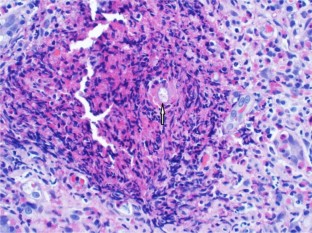

Fig. 2